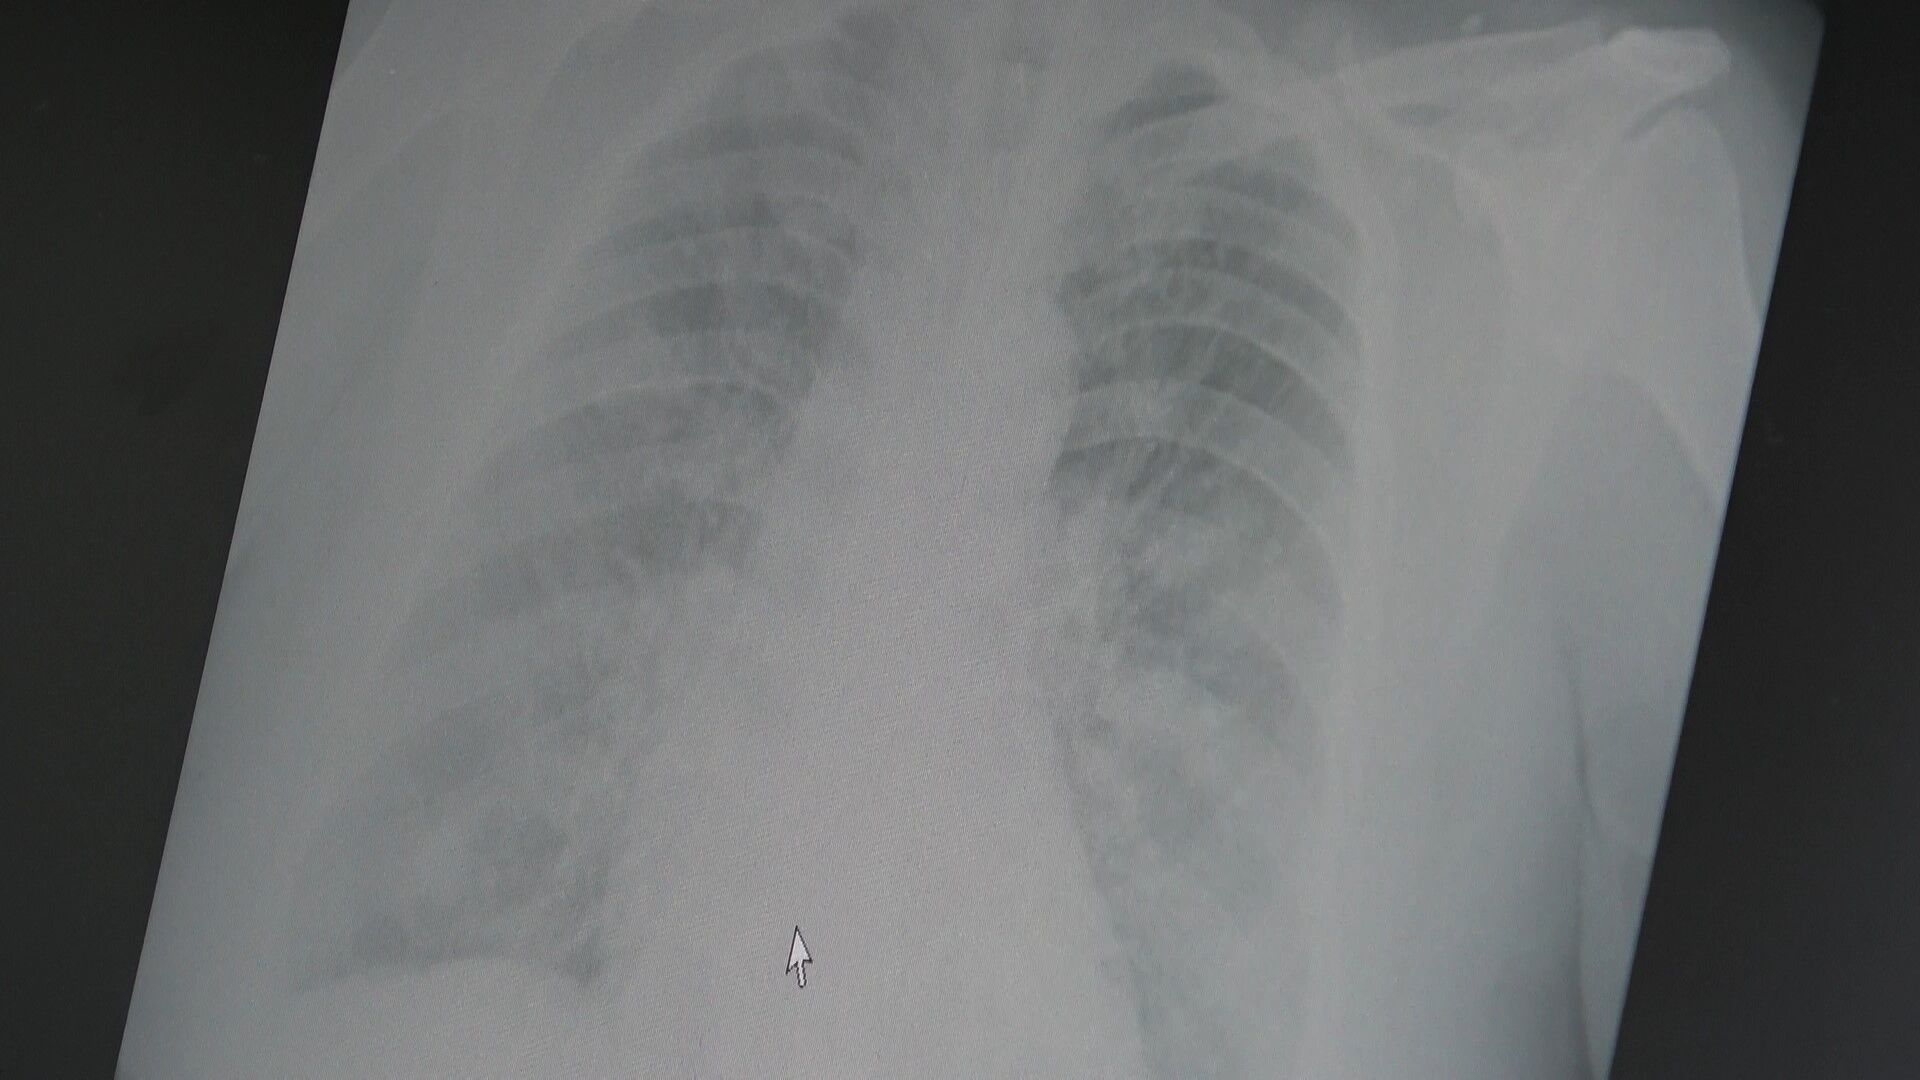

Bu sezon grip vakaları beklenenden daha yoğun yaşanıyor. Göğüs Hastalıkları Uzmanı Prof. Dr. Şevket Özkaya, yapılan sezon sonu değerlendirmelerine göre grip aşılarının yetişkinlerde hastalığı önlemedeki etkinliğinin yüzde 25 ila 30 civarında olduğunu belirtti. Bu oran, son 20 yılın en düşük etkinlik seviyelerinden biri olarak kayıtlara geçti. Uzman, yeni baskın suşun aşının içeriğiyle uyumsuzluğunun, grip vakalarının artışında önemli rol oynadığını vurguluyor.